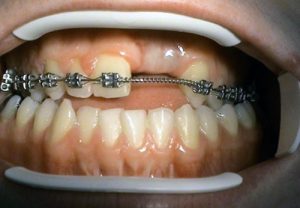

– mini-implants – application in orthodontic

indications